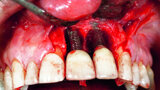

Peri-implantitis therapy